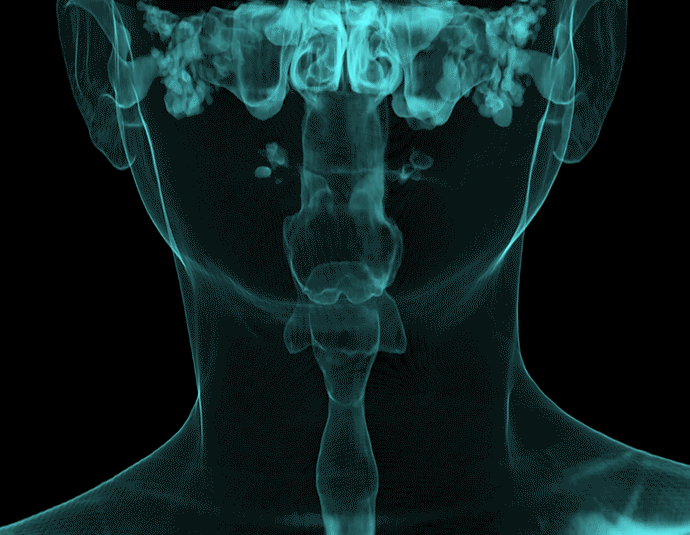

VR體繪制重建

氣道三維影像重建